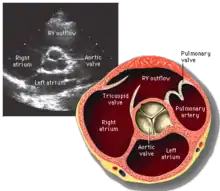

Parasternal short axis (PSAX)

This view is obtained in the same window as the parasternal long, but with the probe rotated 90°. In this view, the aortic valve is seen in cross-section with the right ventricular inflow & outflow tracts visible with the tricuspid valve as well. Pulmonary valve is not visible in this view. Both the right and left atria are visible.

The standard PSAX view is at the level of the aortic valve, but moving the probe along the long-axis can review the LV outflow tract, LV at the base, and LV at the midsection.

Structures visible:

- Aortic valve in short-axis

- Aortic valve dysfunction, aortic sclerosis/stenosis

- Tricuspid valve in long-axis

- Pulmonary valve in long-axis

- Right ventricle, including inflow and outflow tracts

- Left ventricle in short-axis

- Closer to the base can reveal the left ventricular outflow tract

- At the level of the base can show the movement of the mitral valve leaflets in short-axis

- At the level of mid-LV can show papillary muscles